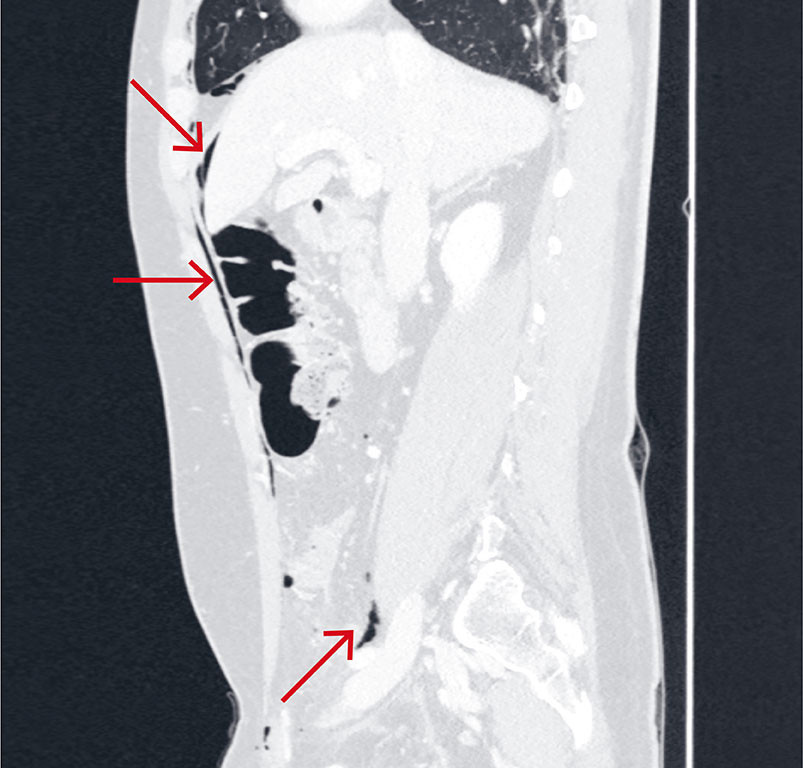

CT av toraks og abdomen/bekken ble tatt rett etter innkomst for å se etter postoperative komplikasjoner. Den viste gass subkutant, mellom fascielagene i bukveggen, i mediastinum, intraperitonealt ved lever samt retroperitonealt (figur 1a og b og figur 2). Det var ingen synlig gass i pleura, og det var ingen tegn til blødning.

På grunn av den spredte gassen og inngrepets art, var iatrogen tarmskade den fremste tentative radiologiske diagnosen. CT-bildene ble sett på av vakthavende radiolog sammen med vakthavende gastrokirurg. Pasientens symptomer var synkope og lett respirasjonspåvirkning, men ingen magesmerter. Buken var bløt uten peritonisme. Til tross for lett feber og leukocytose, var den kliniske vurderingen at tarmskade var mindre sannsynlig. Vi mistenkte derimot at CO2-gassen fra laparoskopien hadde vandret, og at symptomene var forårsaket av capnomediastinum.